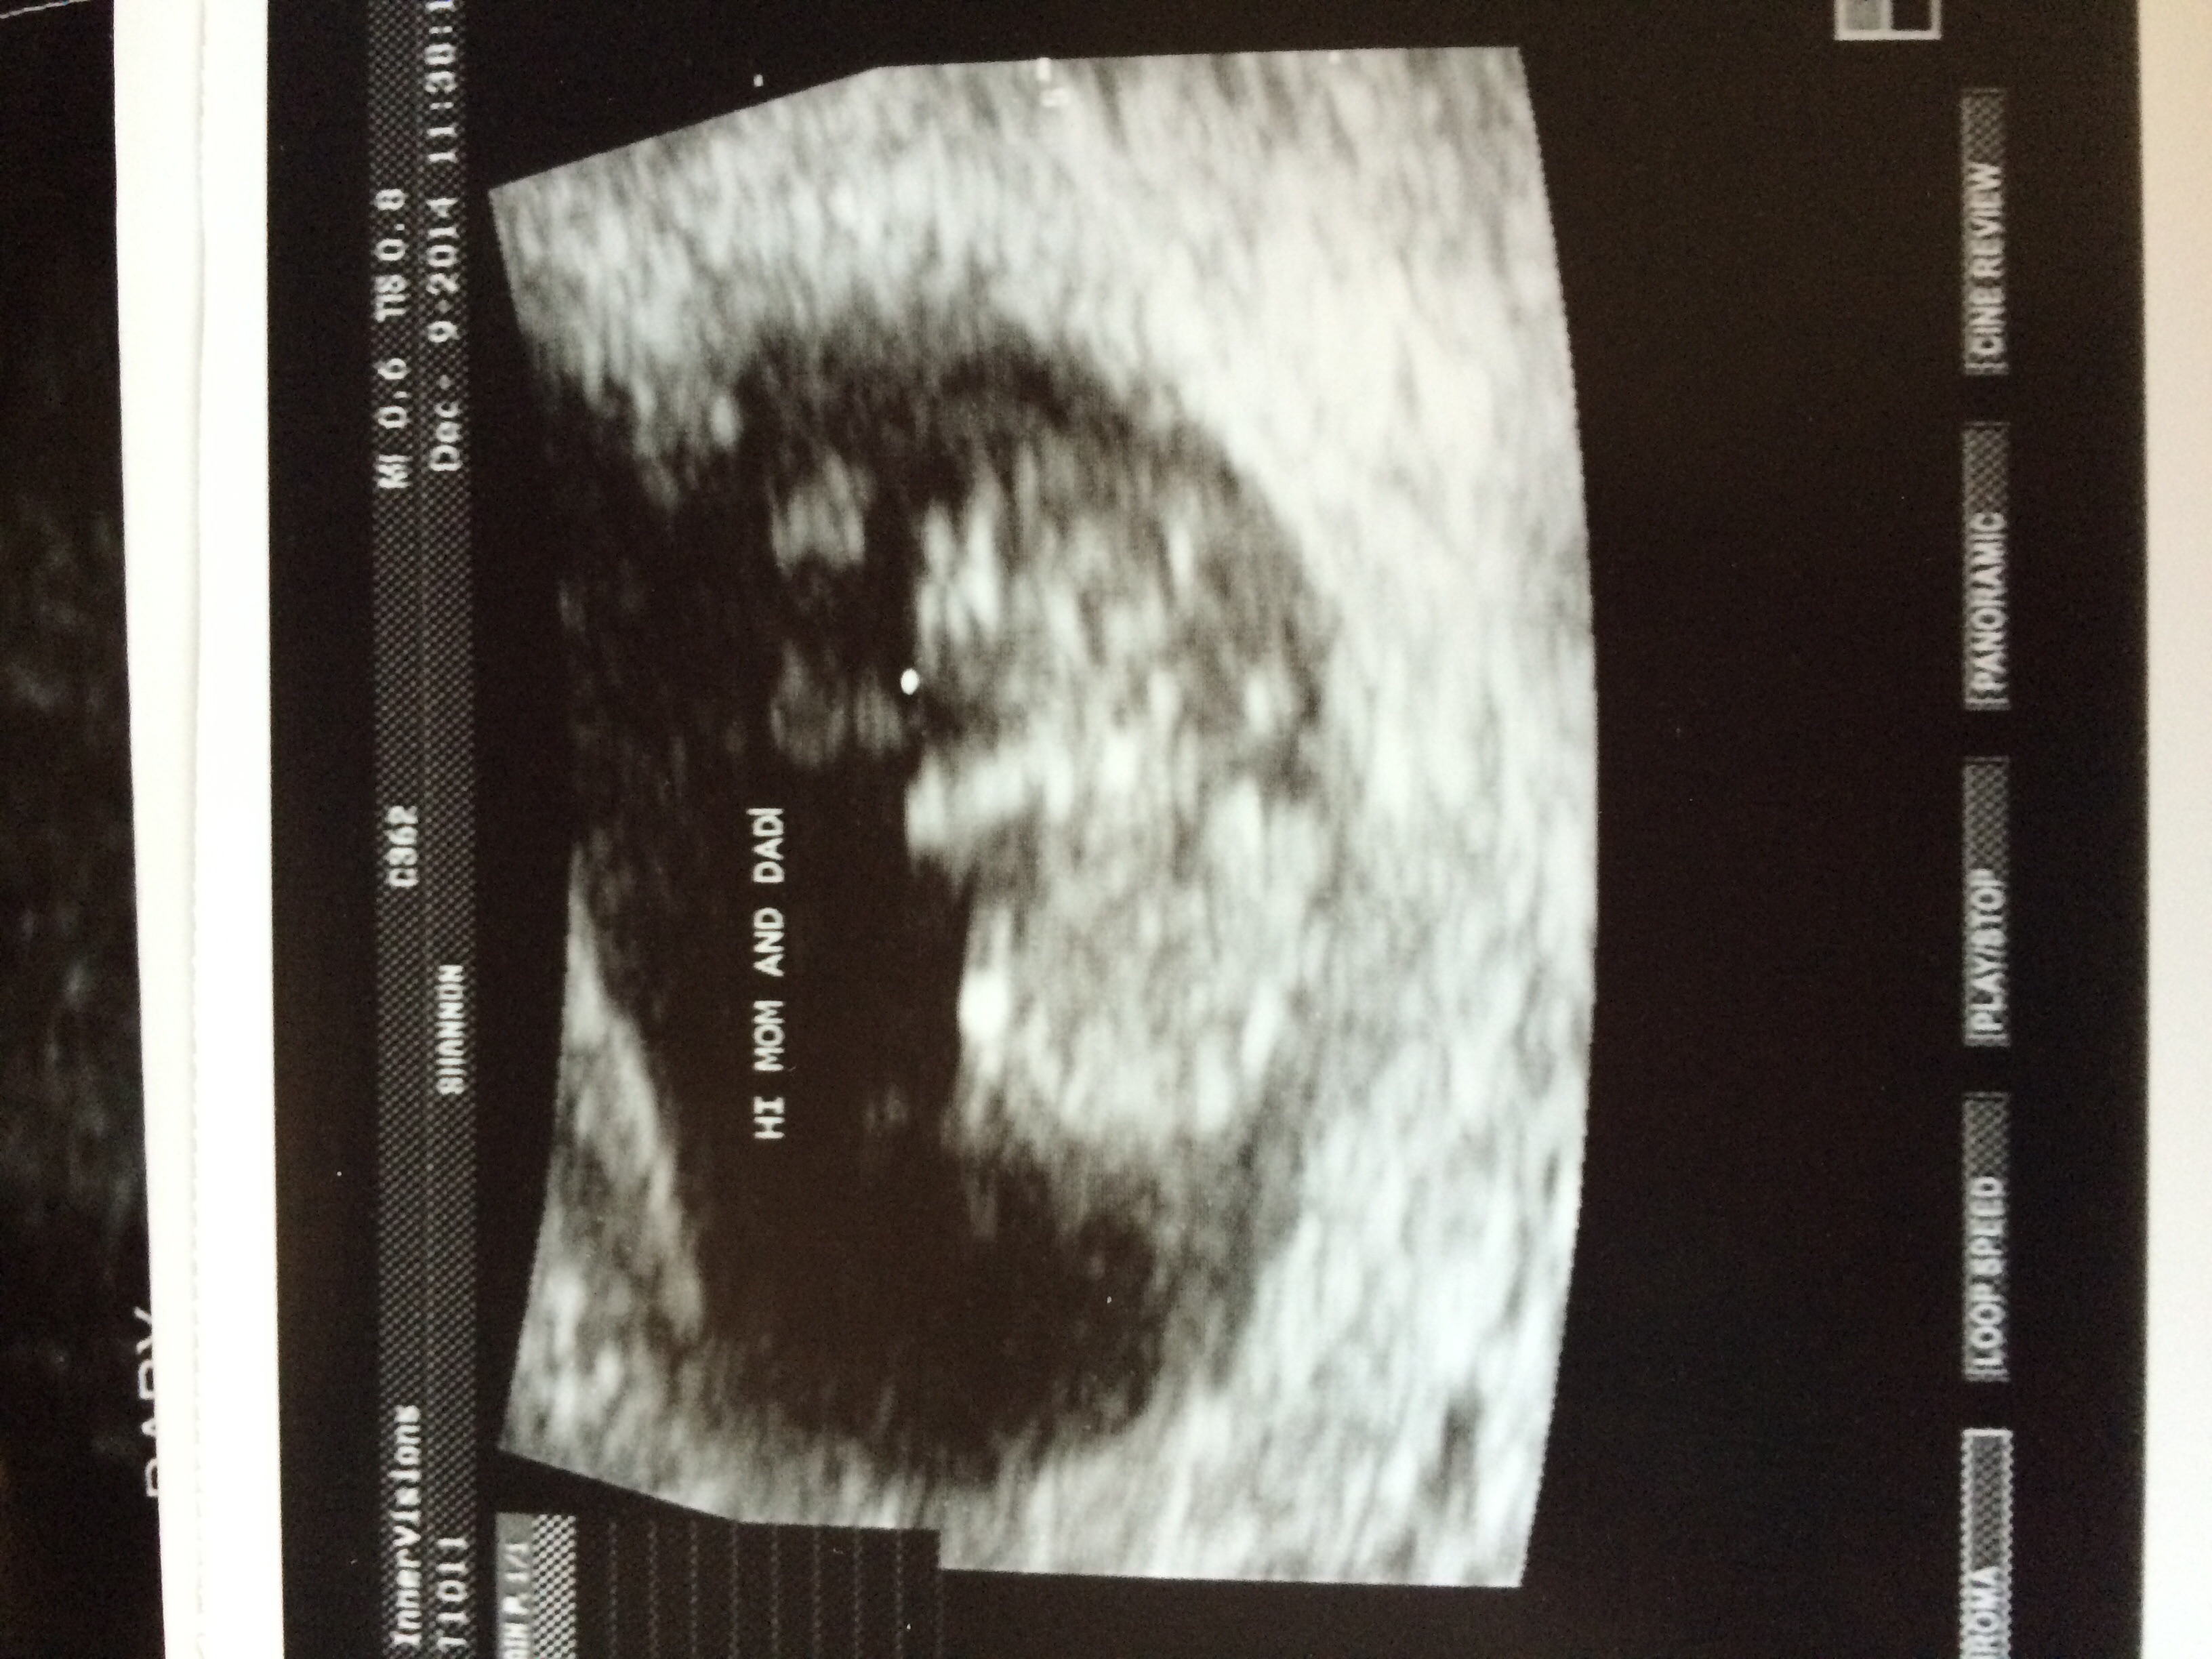

Our whittle bun ;)

Had our ultrasound. Was measuring a week behind but heart rate is strong at 167 and was jumping and moving all over the place! Couldn't be more elated! :-)